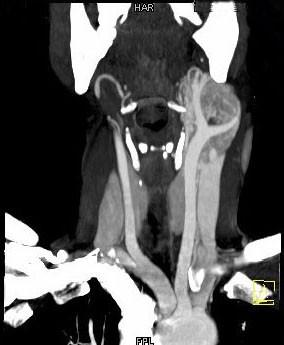

问题 女,39岁,左颈部可扪及一肿块,无发热,无疼痛,CT如图所示,最可能的诊断是()

选项 A.颈部神经鞘瘤 B.颈动脉体瘤 C.颈部神经纤维瘤 D.颈部海绵状血管瘤 E.颈动脉瘤

答案 B